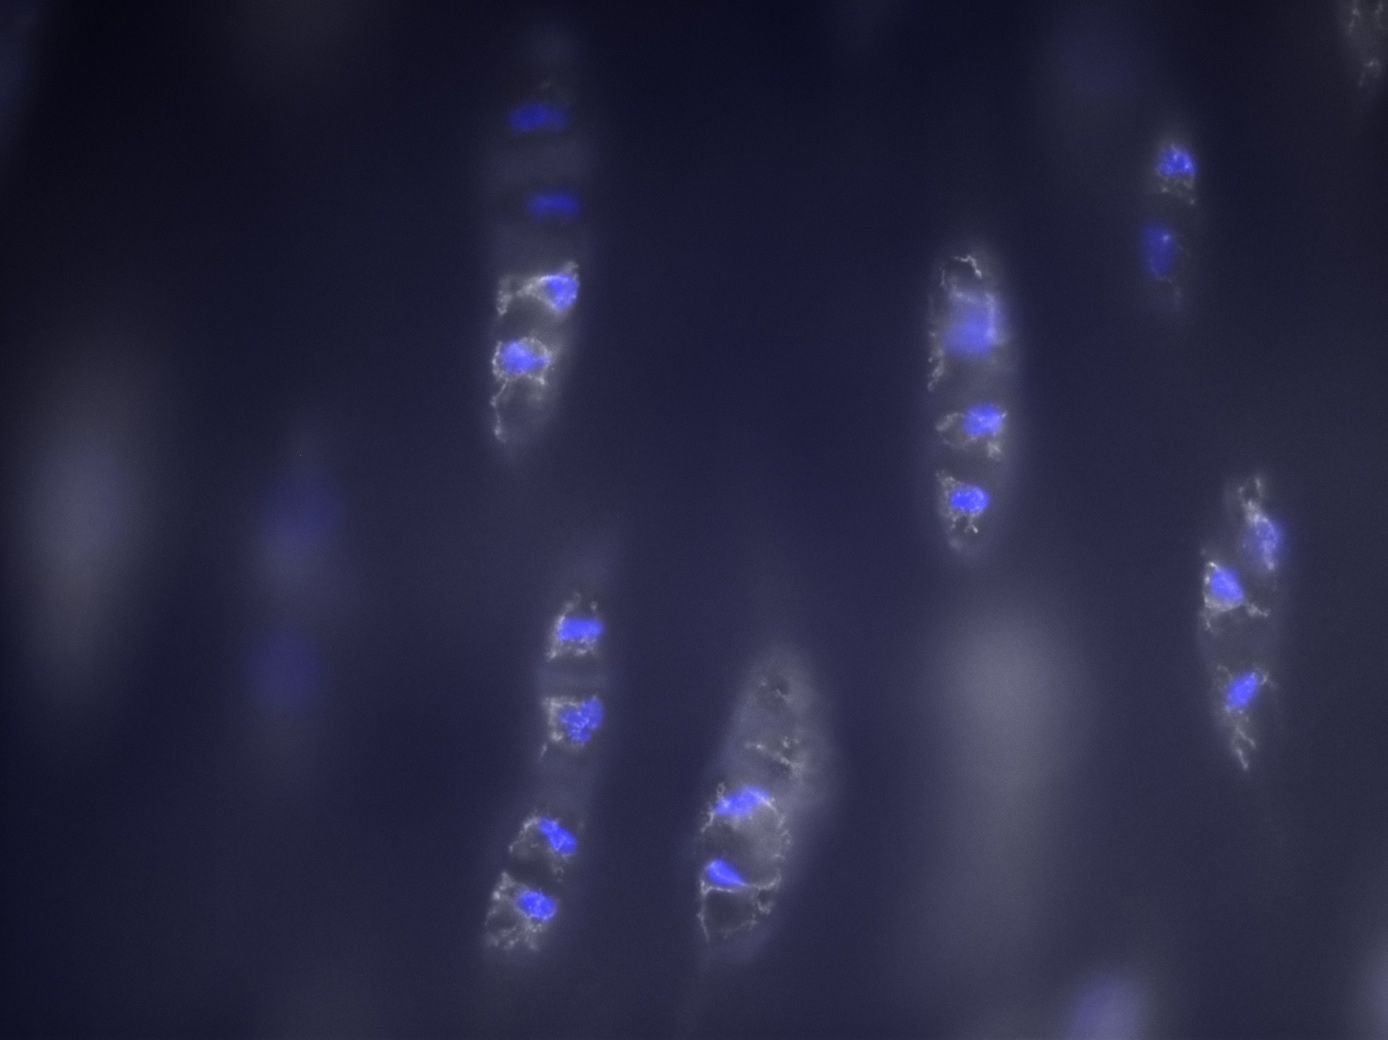

Die perizelluläre Matrix (PCM) spielt eine Rolle bei der Mechanotransduktion von Chondronen. Um zu evaluieren, wie sich eine degenerierte PCM auf die biochemischen Signalwege der Chondrozyten auswirkt, untersuchen wir das Calcium-Signaling der Knorpelzellen. Wir experimentieren mit enzymatisch isolierten Chondronen, deren PCM wir mithilfe von Matrix-Metalloproteinasen teilweise abbauen. Die Zellen werden mittels Atomic-Force-Microscopy (AFM) mechanisch stimuliert und per Fluoreszenzmikroskopie der Calcium-Einstrom gemessen. Ziel ist es, die genaue Rolle der PCM bei der Mechanotransduktion der Zellen zu beleuchten.